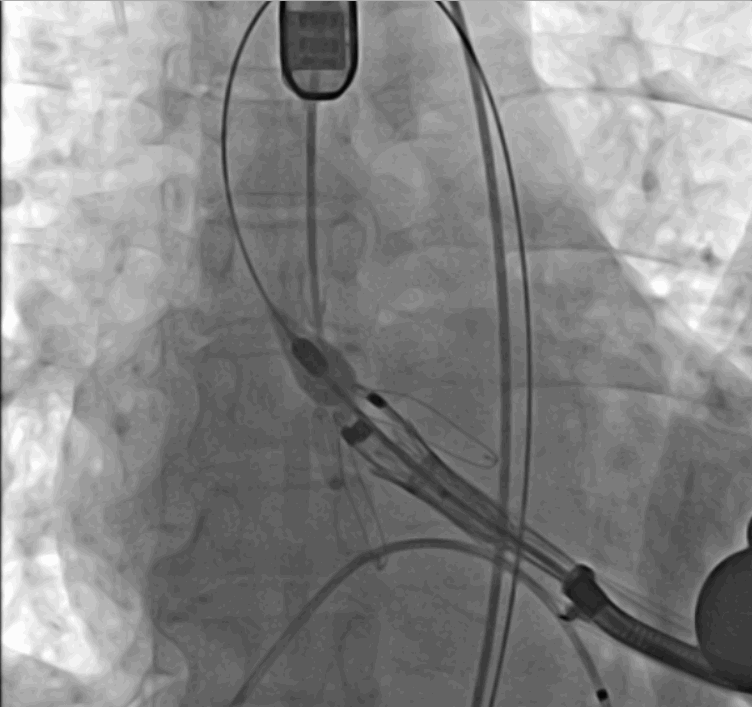

術(shù)前DSA影像圖